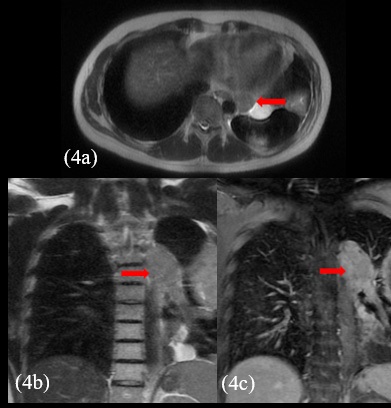

The patient presented with voluminous and symptomatic disease less than six months of chemotherapy end and less than two months of radiotherapy. He restarted with pain in left hemithorax, cough, shortness of breath, lack of appetite and daily vespertine fever. MRI scans in August, 2021 showed new lesions on pleural surfaces beyond the residual mass previously seen (Figures 4a, 4b and 4c). One of the lesions, on the extra-pleural fat adjacent to the diaphragm, extended inferiorly, pushing downward the muscle.

Figure 4: New lesions could be seen in the left hemithorax (arrows) on MRI. The biggest one measured 11.0 x 6.0 x 11.0 cm (375 cm³) and the others 8.0 x 3.5 x 6.5 cm (95 cm³) and 7.0 x 7.0 x 3.0 cm (75 cm³). Note the intense post-contrast enhancement of the lesions.

Before opting for some new agent, empirically, a next generation sequencing analysis was performed on the primary tumor tissue, to guide the subsequent therapy. An amazing pathogenic HMBOX1-ALK gene fusion was identified. Thus, we decide to continue his treatment by administering crizotinib, a tyrosine -kinase inhibitor (TKI) approved in Brazil for usage in lung cancer with ALK translocation. At the beginning of oral therapy, he manifested nausea grade 2, vomit grade 1 and diarrhea grade 2, according to WHO (World Healthy Organization) profile toxicity; all of these symptoms were manageable with regular antiemetic drugs and loperamide. Approximately, one month after the beginning of the new treatment, he reported reduction of chest pain and cough, as well as diminishing of tiredness and dyspnea, which were present only with great effort. The evaluation images with 45 days of crizotinib therapy showed reduction of all the lesions with appearance of necrotic/hemorrhagic areas (Figures 5a and 5b).

Figure 5: Thoracic MRI shows shrinkage of the extent and reduction of the post-contrast enhancement of the lesions (arrows) and appearance of hemorrhage intralesional content (not shown). The biggest one measured 8.5 x 4.0 x 8.0 cm - 140 cm³ (before therapy this value was 11.0 x 6.0 x 11.0 cm - 375 cm³; the others measured 6.0 x 2.5 x 4.0 – 30 cm³, and 6.0 x 5.0 x 2.5 cm - 40 cm³ (before therapy they measured 8.0 x 3.5 x 6.5 cm - 95 cm³, and 7.0 x 7.0 x 3.0 cm - 75 cm³, respectively).